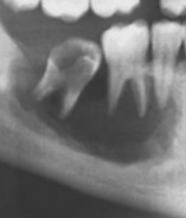

Q

X-ray of skull shows these punched out lesions. The patient is 70 years old, what is the likely diagnosis?

A

multiple myeloma